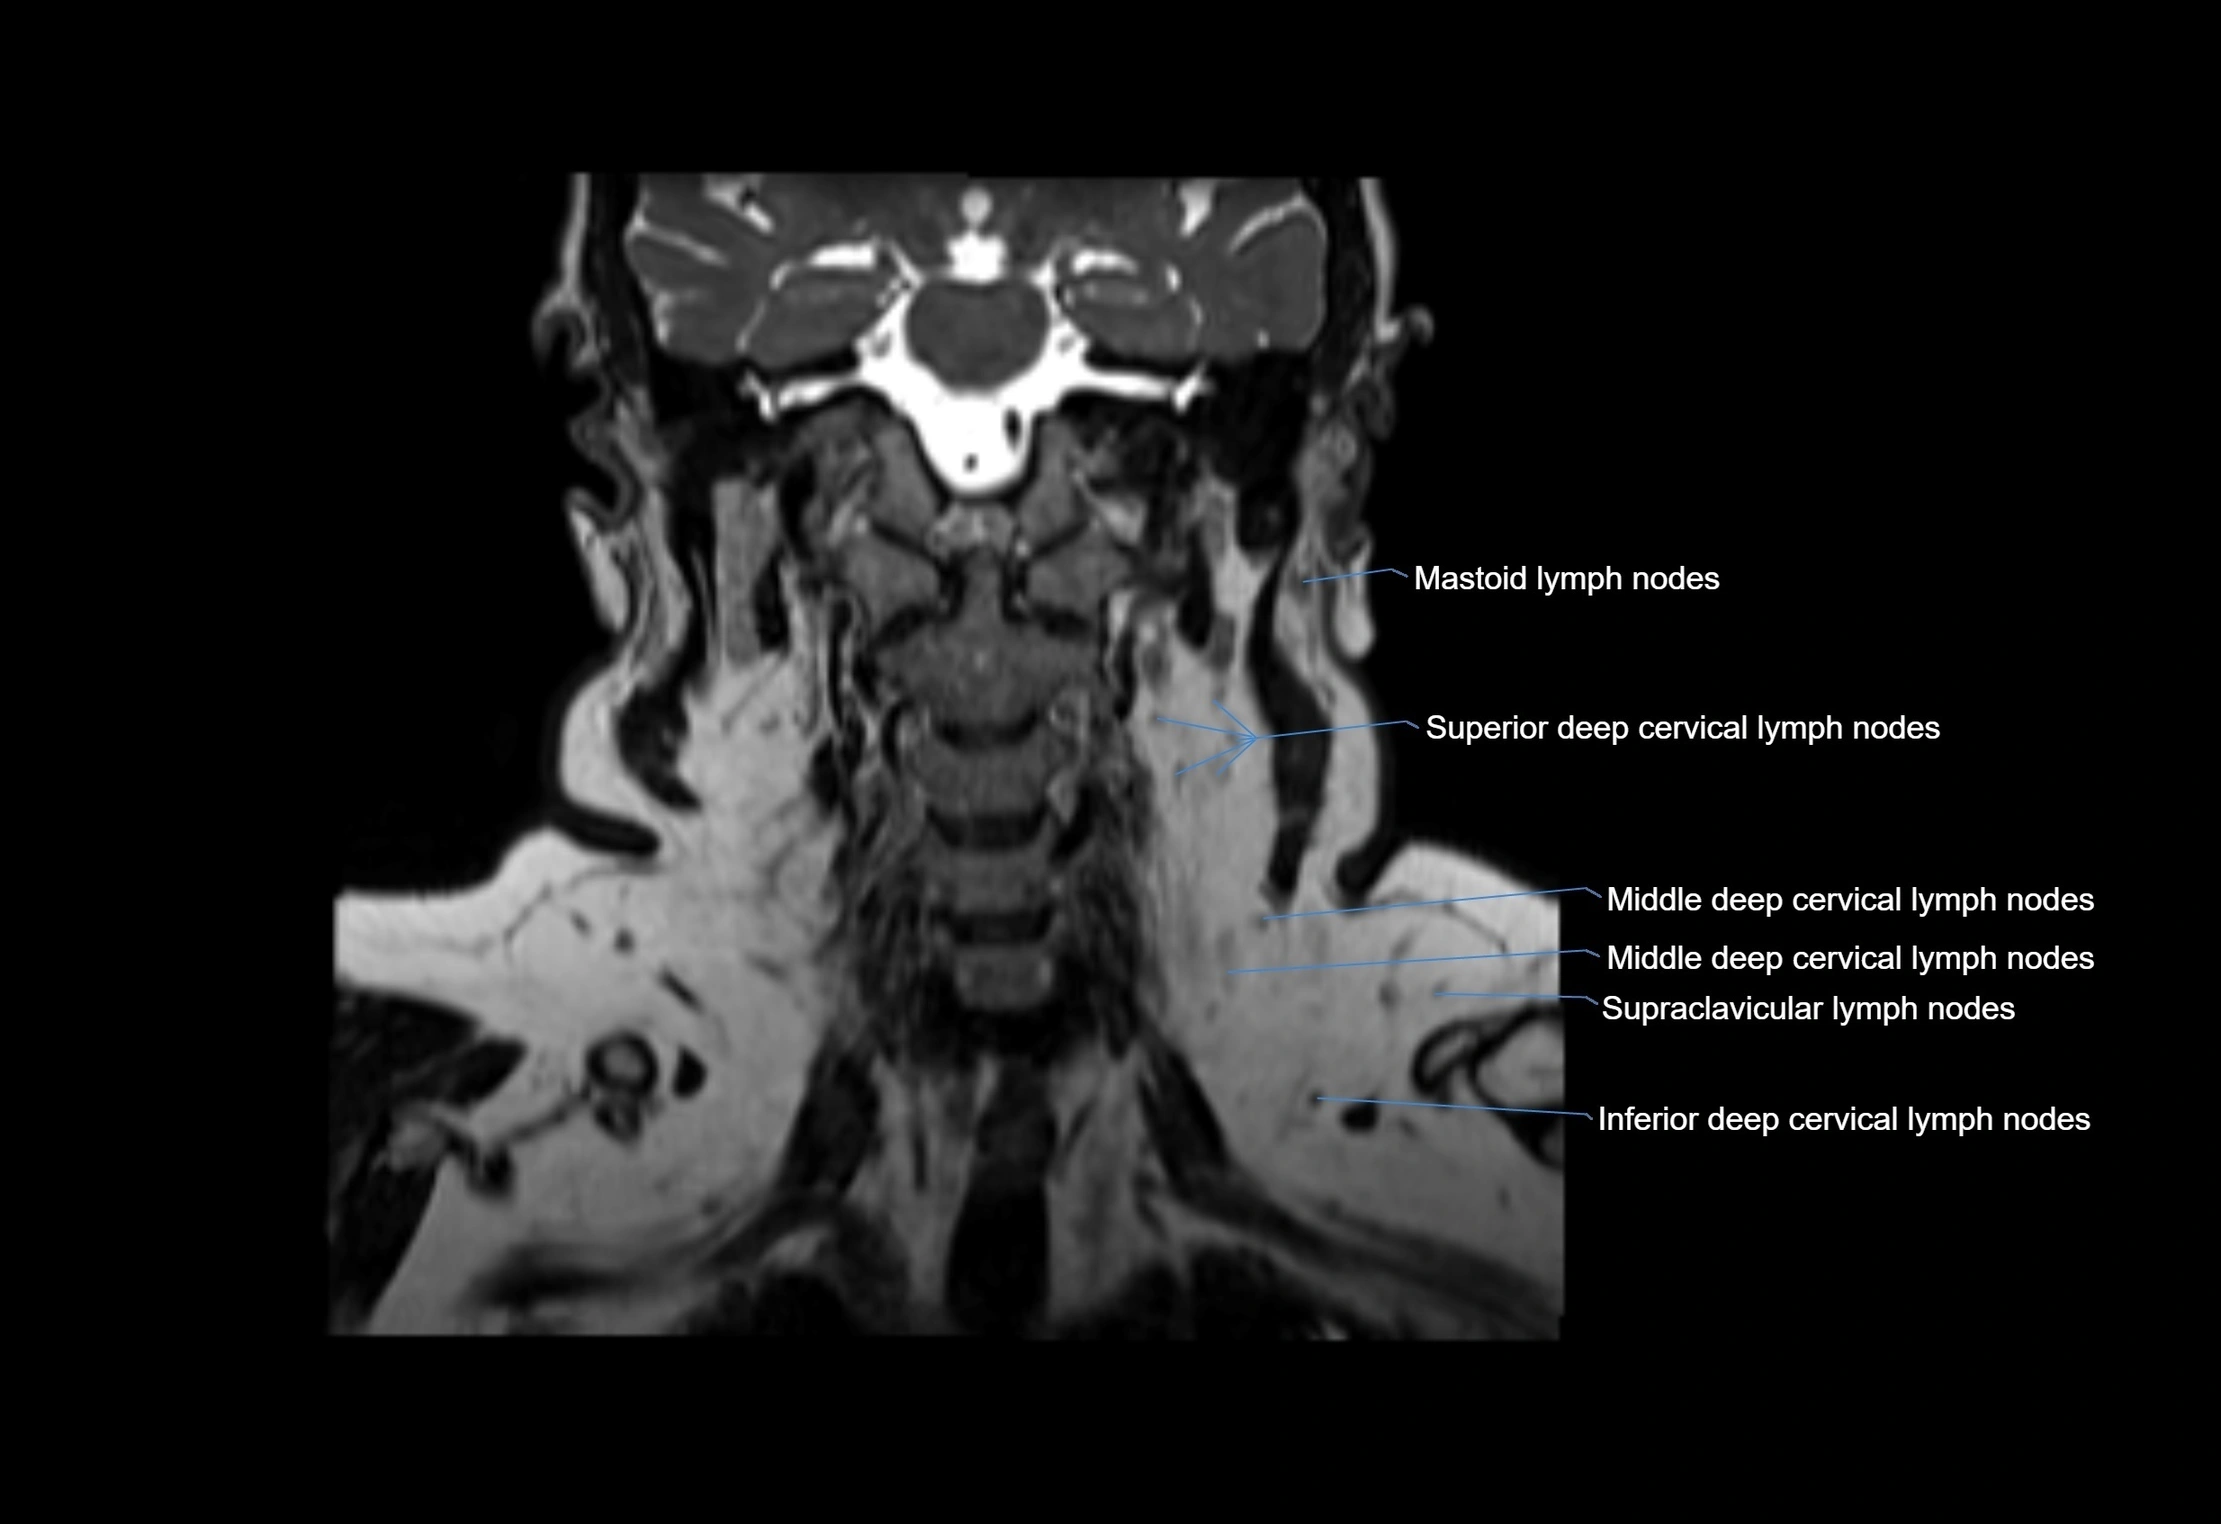

MRI images

image